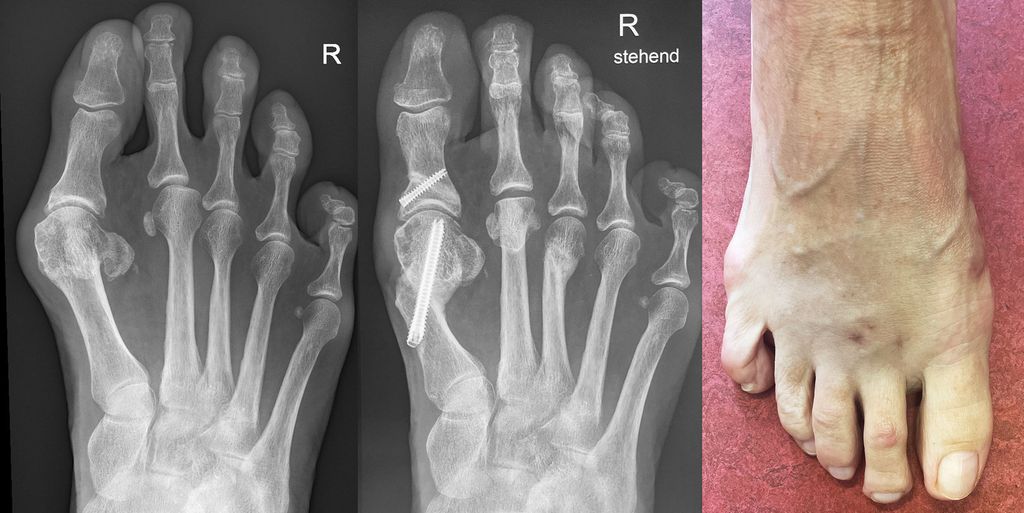

Isolierte Überlängen von Zehen können mit minimalinvasiven Osteotomien an der Grundphalanx sehr gut korrigiert werden (Abb. 6). Bei Fehlstellungen in der Transversalebene wird ebenfalls über eine Stichinzision in Höhe der Fehlstellung eine Kortikotomie durchgeführt und die Fehlstellung durch Schließen der Osteotomie korrigiert (Abb. 7).